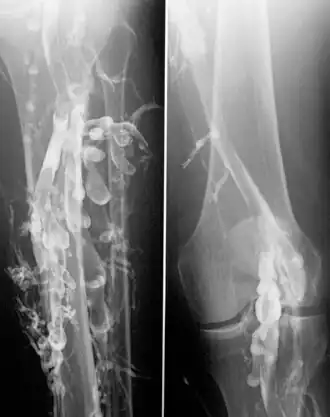

Флебография — это метод медицинского обследования, используемый для изучения венозной системы человека. Позволяет врачам визуализировать кровеносные сосуды и оценить их функцию. Флебография особенно полезна при диагностике и мониторинге различных венозных заболеваний, таких как варикозное расширение вен, тромбозы и другие нарушения кровообращения в венах.

Процедура флебографии обычно включает в себя введение контрастного вещества в вену пациента, после чего снимаются рентгеновские снимки или делается компьютерная томография для визуализации венозной системы. Этот метод помогает врачам увидеть любые аномалии, сужения или блокировки в венах, а также оценить состояние клапанов вен, которые обычно помогают предотвращать обратное течение крови.